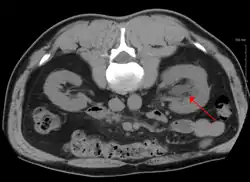

CT scan of bilateral hydronephrosis due to a bladder cancer -

Massive hydronephrosis as marked by the arrow -